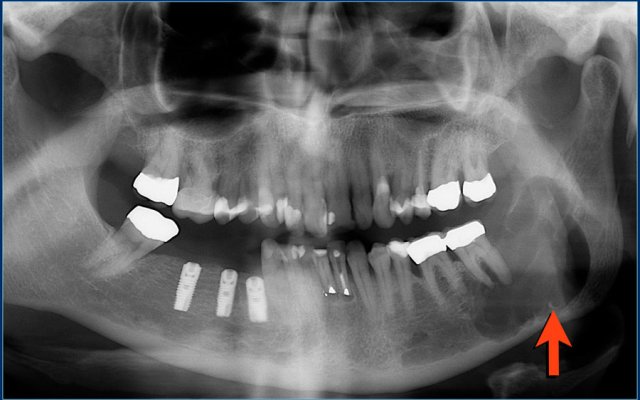

Giant cell granuloma

The mandible is a predilection site of giant cell granuloma.

Here a well-defined lytic lesion in the left mandible.

Final diagnosis: giant cell granuloma of bone.

Diff diagnosis: ameloblastoma.

Here an expansile lytic lesion with thin peripheral bone shell originating from the left mandibular head.

The axial T2-weighted image with FS shows multiple cavities with fluid levels consistent with secondary ABC.